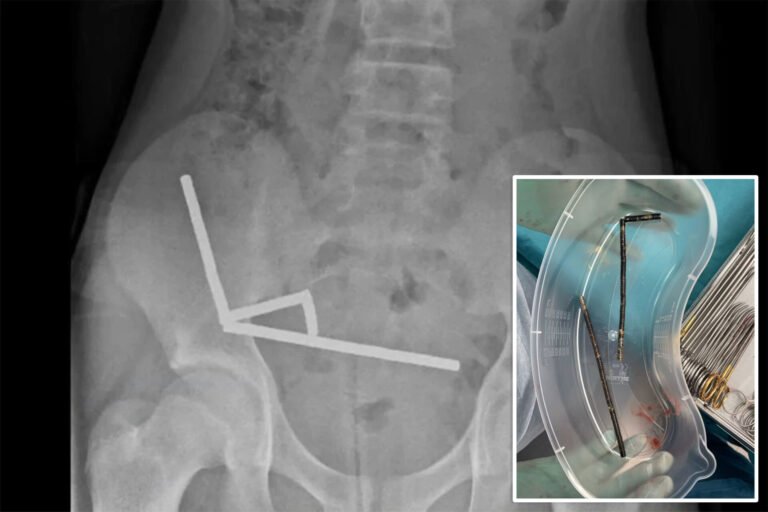

13-year-old boy has emergency surgery after swallowing 100 magnets

The high-powered magnets are believed to have been purchased from the Chinese shopping site Temu.